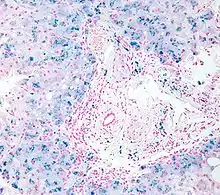

In histology, histopathology, and clinical pathology, Perls Prussian blue is a commonly used method to detect the presence of iron in tissue or cell samples.[1]: 235 [2][3][4] Perls Prussian Blue derives its name from the German pathologist Max Perls (1843–1881), who described the technique in 1867.[2] The method does not involve the application of a dye, but rather causes the pigment Prussian blue to form directly within the tissue.[5] The method stains mostly iron in the ferric state which includes ferritin and hemosiderin, rather than iron in the ferrous state.[6]

Perls's method is used to indicate "non-heme" iron in tissues such as ferritin and hemosiderin,[6] the procedure does not stain iron that is bound to porphyrin forming heme such as hemoglobin and myoglobin.[2] The stain is an important histochemical stain used to demonstrate the distribution and amount of iron deposits in liver tissue, often in the form of a biopsy.[6][7] Perls's procedure may be used to identify excess iron deposits such as hemosiderin deposits (hemosiderosis) and in conditions such as hereditary hemochromatosis.[8] Perls Prussian blue is commonly used on bone marrow aspirates to indicate levels of iron storage[4] and may provide reliable evidence of iron deficiency.[7]

Perls did not publish a detailed procedure other than indicating a dilute potassium ferrocyanide solution was applied to the tissue followed by hydrochloric acid.[2] Ferric iron deposits in tissue (present mostly as ferric iron within the storage protein ferritin) then react with the soluble ferrocyanide in the stain to form the insoluble Prussian blue pigment (a complex hydrated ferric ferrocyanide substance). These deposits are then visualizable microscopically as blue or purple deposits.[9]

Many methods of performing Perls Prussian blue stain for iron have been published, [2] Drury and Wallington (1980) give a protocol that uses a mixture of 1 part 2% hydrochloric acid and 1 part 2% potassium ferrocyanide that is applied to the section for 20–30 minutes followed by a rinse in distilled water and application of a counterstain such as eosin, safranin or neutral red.[5]